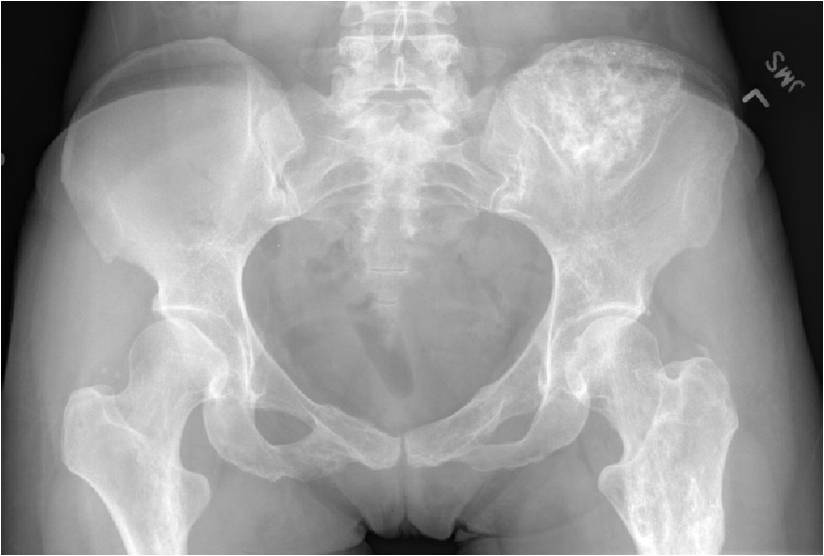

Sites:

- 50% involve hands and feet (mostly phalanges)

- Proximal Humerus, Femur most common long bones

- Enchondromas of the pelvis, vertebrae and ribs are uncommon

- Almost all hyaline cartilage tumors of the pelvis are considered malignant based on anatomic location no matter what the pathology shows. These tumors will ultimately grow locally and have the potential to dedifferentiate or change into a higher grade chondrosarcoma.

- Localized, radiolucent defect usually with punctate calcifications

- Calcifications are typical but not always present

- Matrix may demonstrate various degrees of calcification

- Calcifications are stippled, punctate, popcorn like calcifications and “Ring and Arc” calcifications

- Cartilage tumors grow in a lobular manner. The perimeters of the lobules undergo

- enchondral ossification that may calcify. If the entire perimeter of the lobule calcifies it appears

- radiographically as a “Ring”. If a portion of the perimeter of a lobule calcifies it forms an “Arc” on

- an X-ray.